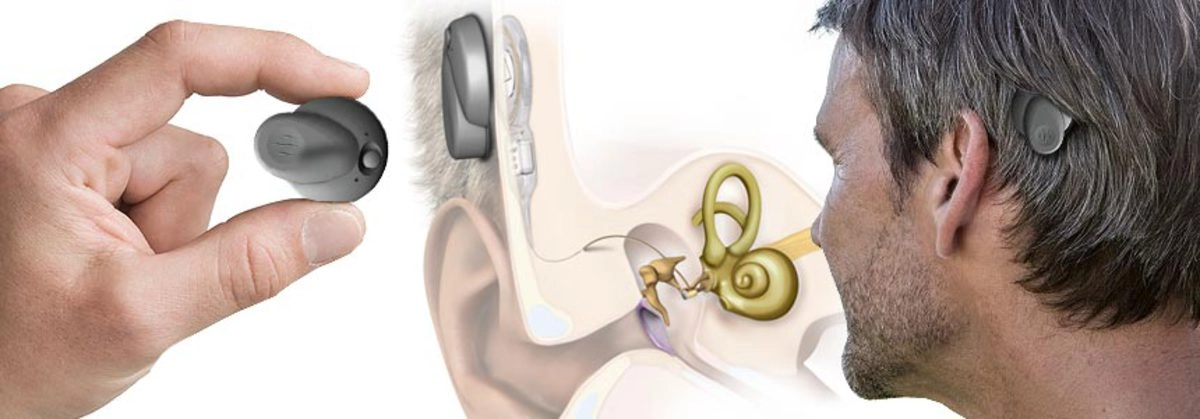

Современные слуховые аппараты при сенсоневральной тугоухости